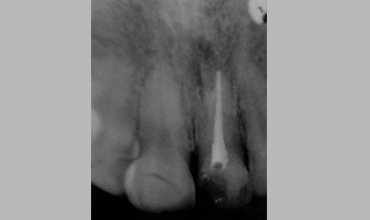

Management Of Fractured Central Incisor With Biological Post